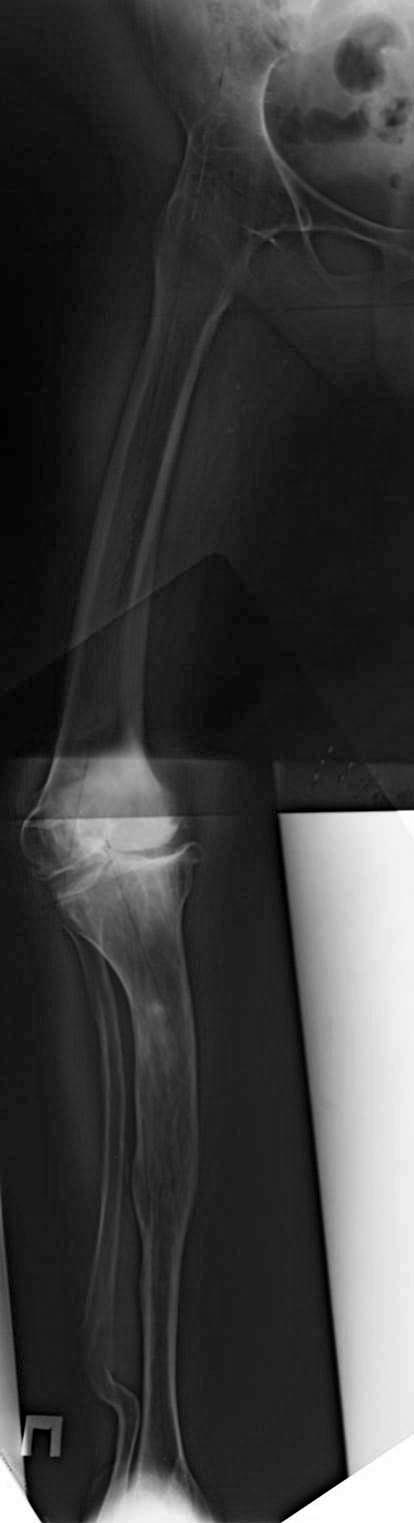

Артродез тазобедренного сустава неизвестной давности и сложная компенсаторная деформация конечности. Для принятия решения одной проекции не хватает. Дополнительно: общий таз и на всю длину конечности рентгенорамма с включением голеностопного. Отдельные снимки тазобедренного и коленного суставов.

На основании сравнительных данных механической оси конечности принимается решение. После длительно замкнутых суставов механика конечности адаптирована к этим условиям, и, нарушая, получаем совсем другие показатели.

В аттаче первичном почему-то темный снимок. Выкладываю поярче.

Рисунок2.jpg

150KB (154565 bytes)